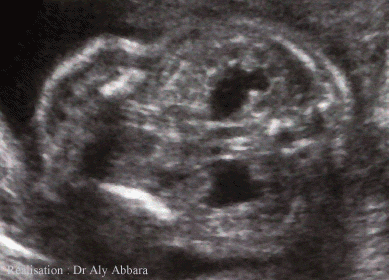

Coupe abdominale frontale passant par les reins à 24 semaines d'aménorrhée

Elle montre les deux reins fœtaux avec une dilatation des bassinets

Le caryotype fœtal est normal ; dilatation stable durant toute la grossesse